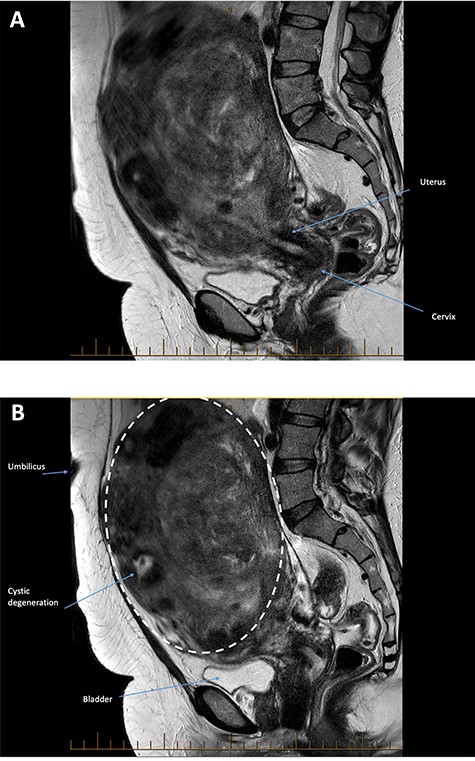

On examination, her vital signs were within normal limits. Her uterus was palpable to just below the xiphisternum and her abdomen was mildly tender. A full blood count was performed which showed haemoglobin of 91 g/l with a mean corpuscular volume of 73 fL. Renal function was normal. A pelvic ultrasound revealed a uterus that was grossly enlarged by multiple fibroids, extending above the level of the umbilicus and into the right hypochondrium. The largest fibroid was a broad-based right fundal exophytic subserosal fibroid measuring 147 × 114 × 180 mm. There was a large posterior intramural fibroid measuring 124 × 111 × 103 mm, in addition to multiple other fibroids. The patient was further assessed with magnetic resonance imaging (MRI; Fig. 1A and B), which re-demonstrated marked uterine enlargement secondary to the fibroids, some of which demonstrated areas T2 hyperintensity reflecting cystic degeneration. The largest exophytic fibroid at the right lateral uterine fundus (dotted outline) extended superiorly to abut the inferior right hepatic lobe, compressing the right kidney and displacing bowel loops to the left upper quadrant. The largest intrauterine fibroid compressed the endometrial cavity and displaced it rightward. No malignant or aggressive features were present. These imaging findings were consistent with an ultrasound and MRI performed in the USA ~18 months prior.

(A and B): Sagittal images from a T2 weighted sequence. Marked enlargement of the uterus secondary to fibroids. The largest fibroid arises at the uterine fundus (dotted line) and extends into the upper abdomen above the level of the umbilicus. It contains areas of focal high T2 signal reflecting cystic degeneration. No malignant or aggressive features are present.